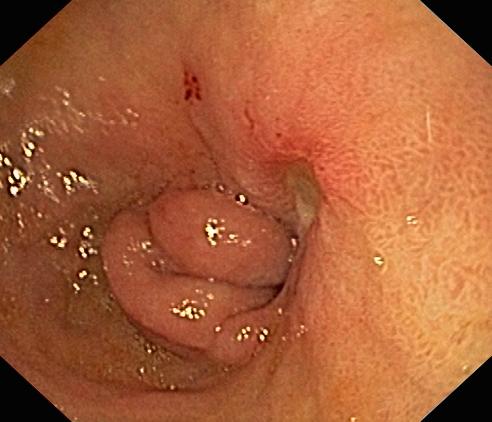

Wrzód trawienny